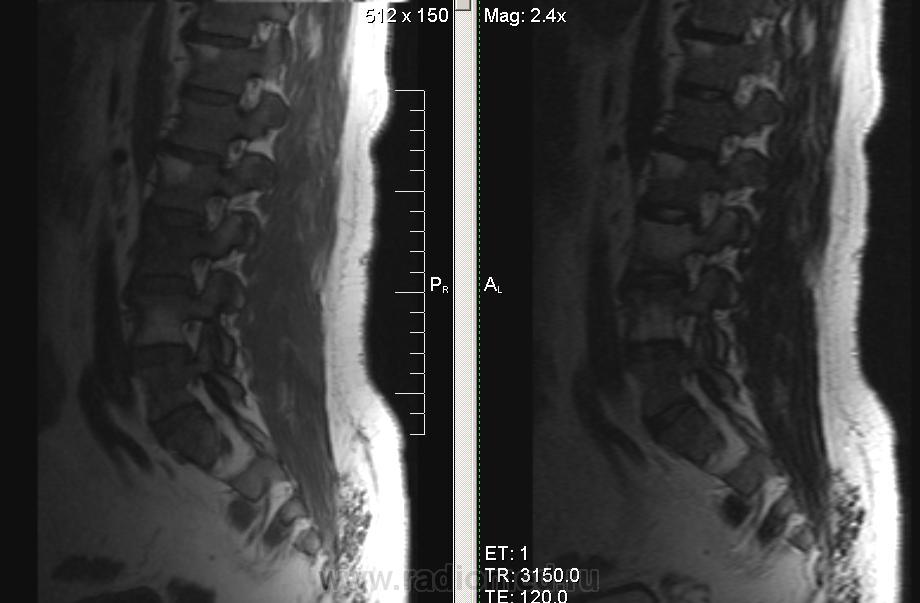

Мужчина, 1974г.р. В течении полугода боли в правой ноге, пояснице. Коллеги, подскажите, пожалуйста, что за системная болячка такая. В грудном отделе - то же самое.

серонегативная спондилоартропатия (?)

Ага, по ссылке Бехтерева.. Тока обычно изменения в области дугоотростчатых суставов и рёберно-позвонковых. У меня было первой мыслью, но суставов на представленных снимках нет.

Сакроилеит. Так что спондилоартрит наиболее вероятен. И боль в правой ноге понятна. Я если у молодых людей причины для корешковых болей не вижу, делаю программу на крестцово-подвздошные суставы. Единственно, в позвоночнике обычно бывает отёк костного мозга апофизов, дугоотростчатых и рёберно-позвонковых суставов.